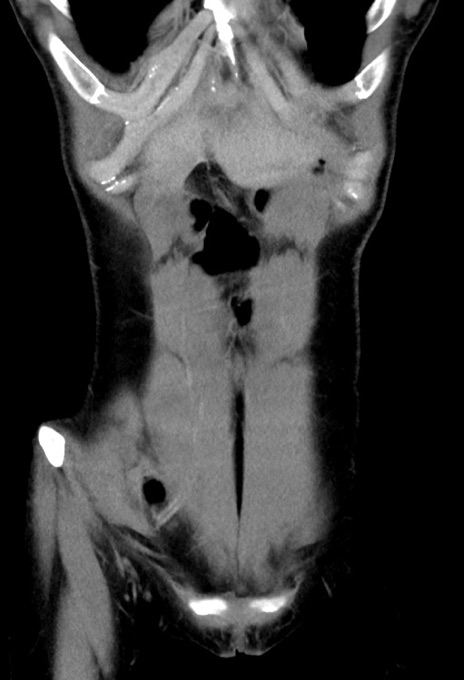

症例17(冠状断像)

【症例】20歳代女性

【主訴】嘔吐、下腹部痛

【現病歴】昨日夕食後に嘔吐し下腹部痛が出現。本日になっても嘔吐持続し改善しないため来院。

【身体所見】意識清明、BT 37.2℃、BP 108/67mmHg、腹部:平坦、やや硬、下腹部正中から右にかけて圧痛あり、反跳痛軽度あり、tapping pain(+)。

【データ】WBC 13600、CRP 14.94